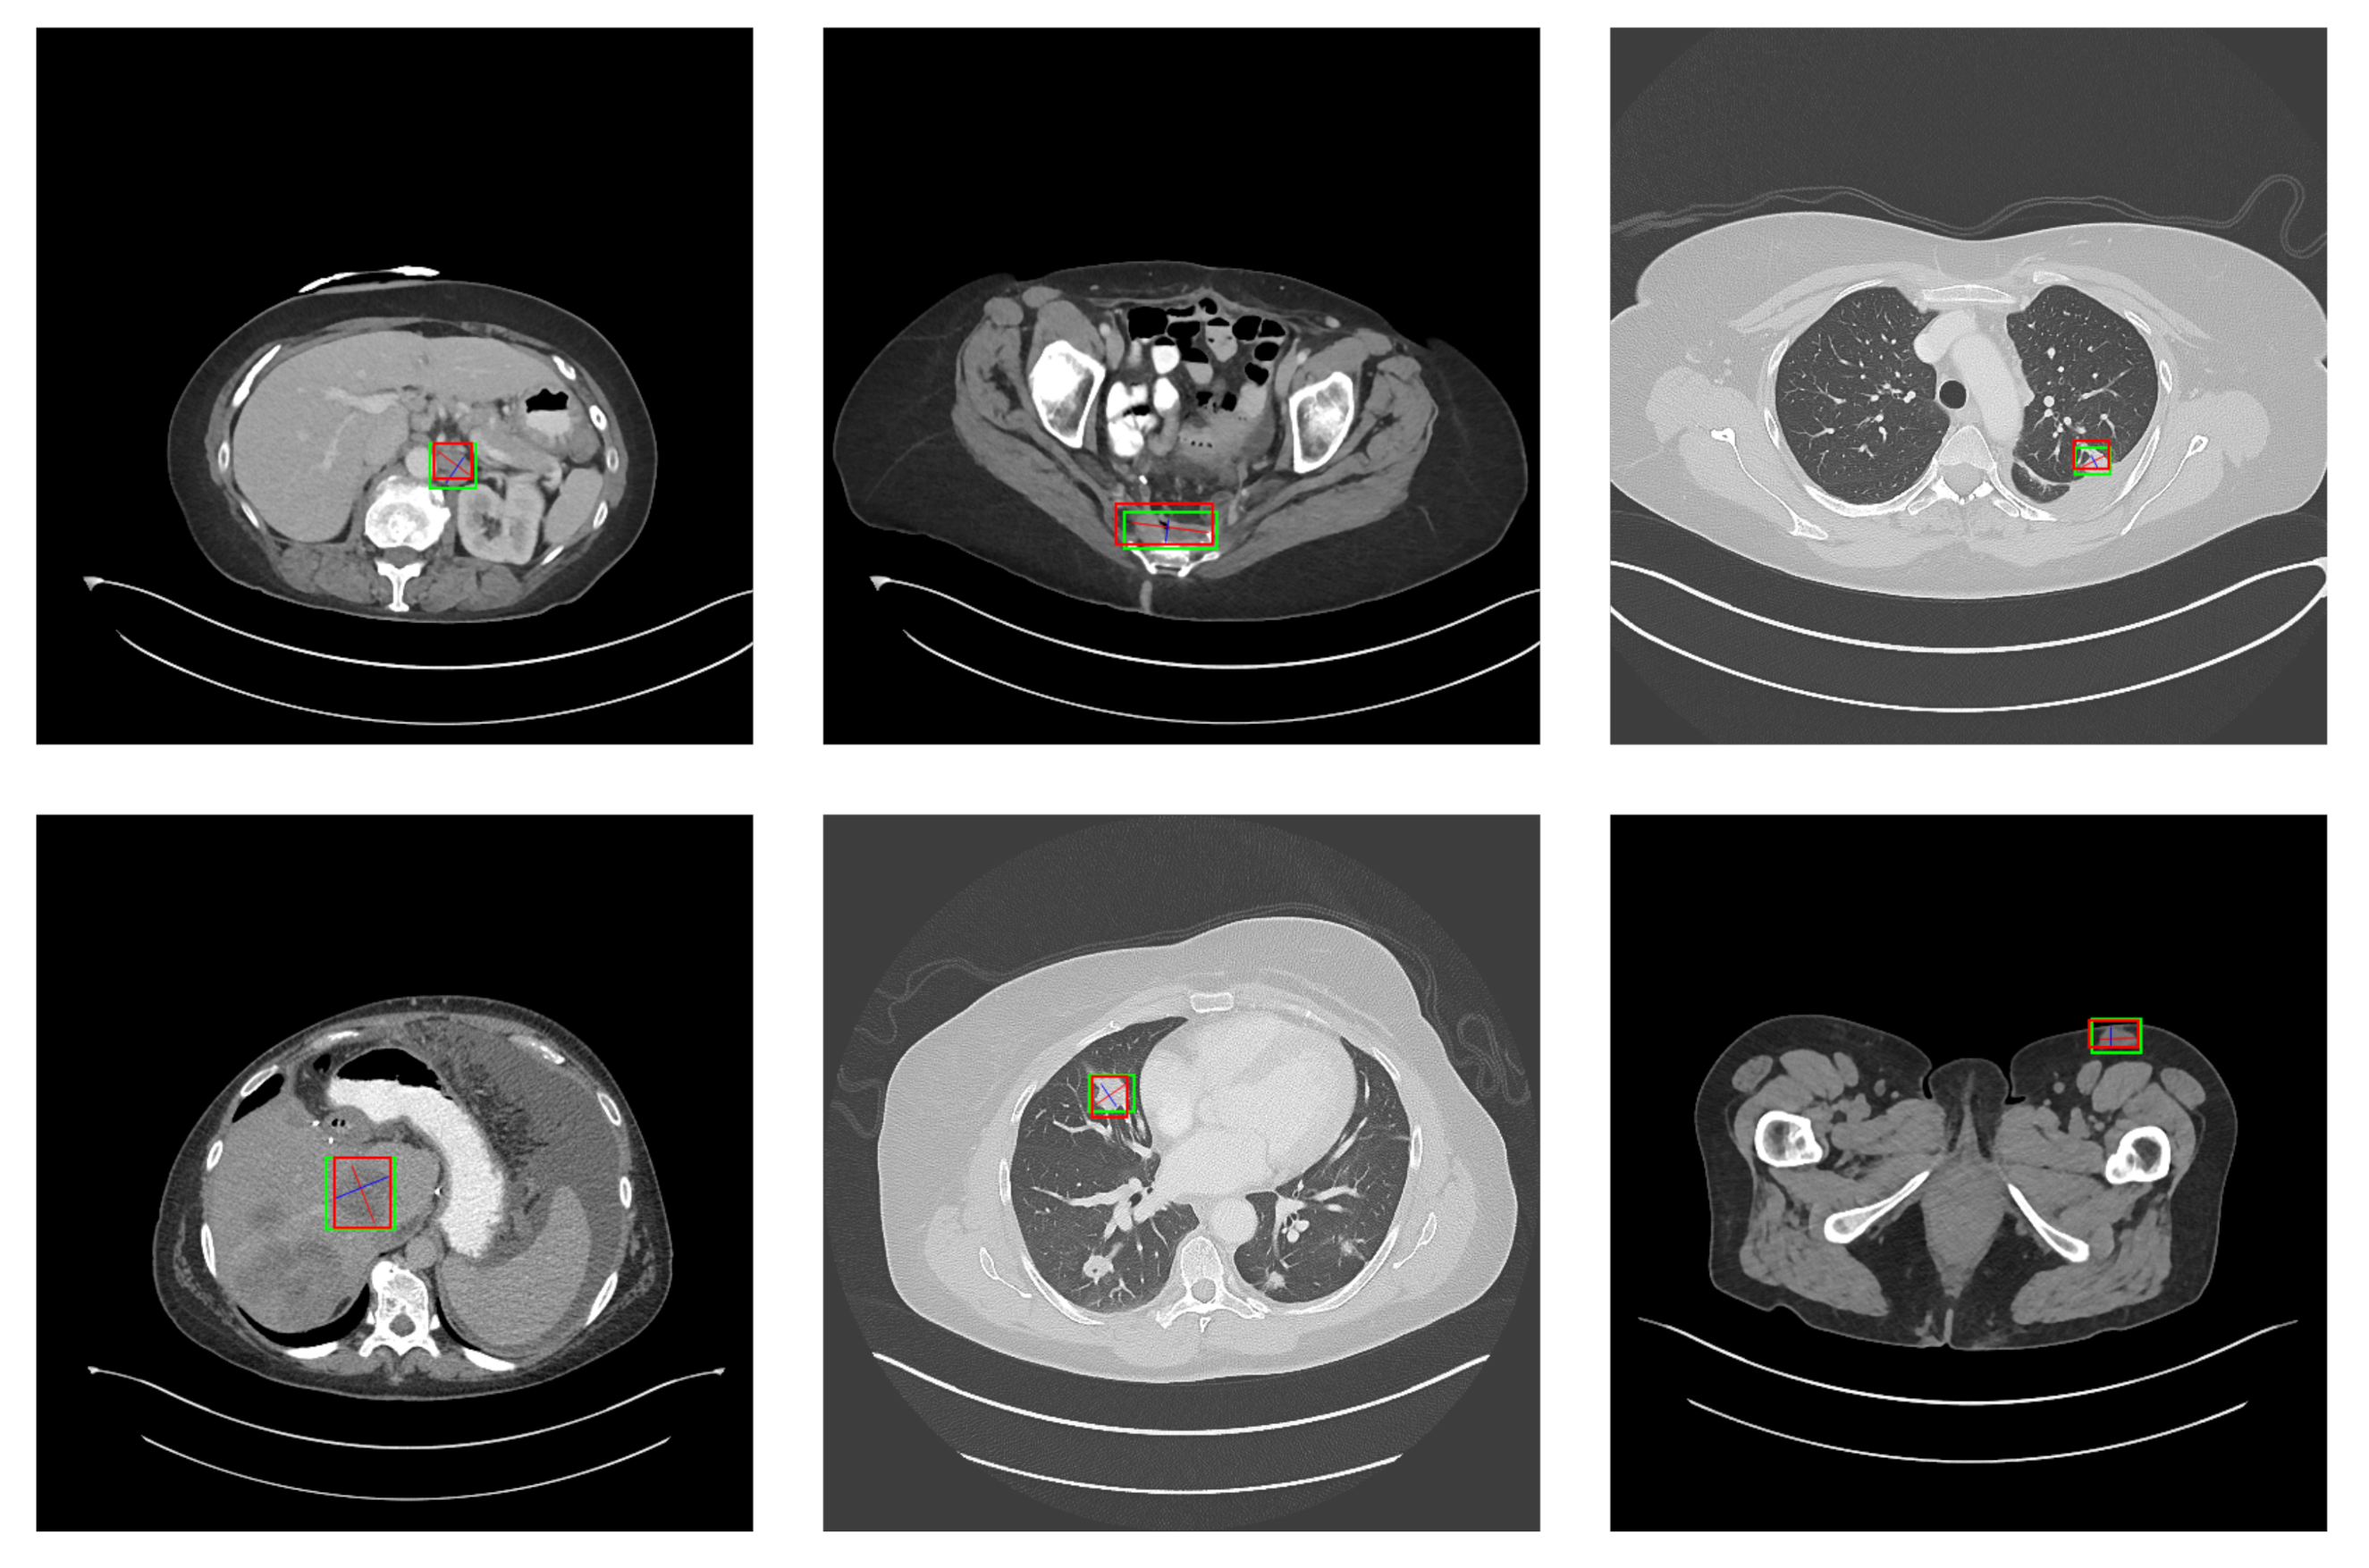

5.2. Detection Results

For further comparison, we extracted six images from the CT image series of DeepLesion. These images were taken from different sites of lesions and different areas of lesions, showing the detection results of the comparison model as comprehensively as possible. Figure 10, Figure 11, Figure 12, Figure 13, Figure 14, Figure 15, Figure 16, Figure 17, Figure 18 and Figure 19 show the detection results. All green boxes represent ground truth; red boxes denote predicted bounding boxes. It can be seen that Faster-RCNN performs very poorly on small lesions and lesions that are not easy to identify, while YOLO v3, YOLO v4, and SSD series perform relatively well. However, the aspect regression of the bounding box at small lesion locations is still not accurate. On the other hand, EfficientDet, Mask-RCNN, and YOLO v5 perform relatively well and detect lesions accurately. This may be related to the attention extraction module in these networks.

Figure 18.

The detection results of SGDN 300 in the DeepLesion dataset. The green box marks the location of the lesion.

Figure 19.

The detection results of SGDN 512 in the DeepLesion dataset. The green box marks the location of the lesion.

Our model, especially SGDN 512, outperforms the previous models by detecting lesions with high accuracy for non-minimal lesions. Although there is still room for improvement, it has outperformed other models. On the one hand, we augment the image with the GAN model before it is fed into the backbone. On the other hand, we add the GAN model to the attention extraction module of the model, which can significantly improve the model’s robustness.

According to Figure 10, Figure 11, Figure 12, Figure 13, Figure 14, Figure 15, Figure 16, Figure 17, Figure 18 and Figure 19, the proposed model produces the most comprehensive detection results compared to other models. However, there are still a few cases where the shortcomings of SGDN can be seen: the arrows in Figure 19 show that our model is still not accurate at the edge of the lesion. In addition, from these figures, we can see that all the comparison models perform very poorly at the site of arrow A. The difference between the predicted box and the ground truth given by our model at arrow A is the largest compared to other recognition results.